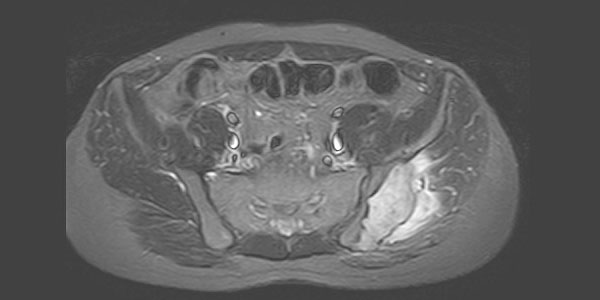

Kondrosarkom - Kıkırdak Doku Kaynaklı Kemiğin Kötü Huylu Tümörü

Kıkırdak doku kaynaklı kemiğin kötü huylu tümörüdür. Sıklıkla 40 yaş sonrası ortaya çıkar. Erkeklerde daha sık görülür. En sık pelvis, kalça ve omuz çevresinde saptanır. Uzun kemiklerin sıklıkla metafiz bölgesinde yerleşir.